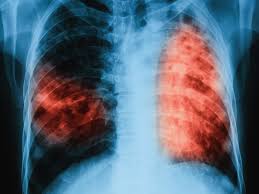

« Tuberculosis